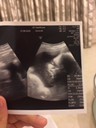

ภาพอัลตร้าซาวด์

มีใครซาวตอน33+5แล้วเห็นหน้าน้องมั้ยค่ะของเราเห็นประมาณนี้